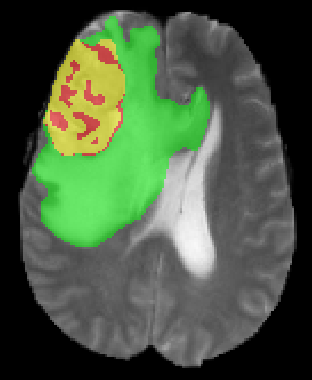

We argue that the sub-optimal paradigm of processing different abstractions within a single CNN pipeline can be remedied through the effective processing of information in a structured manner. Consequently, we devise strategies for disentangling the edge and texture information within a single training pipeline. Figure 2 illustrates how our proposed module, dubbed EG-CNN, can be paired with any existing CNN encoder-decoder to improve segmentation quality near intensity edges. We have applied our EG-CNN to the tasks of brain and liver tumor segmentation in medical images (Figure 3).

(1) Brain MR (2) Liver MR (3) Liver CT (4) Lung CT

We first introduce a method for connecting the output of a CNN to an ACM, yielding a model for the precise delineation of lesions, to which we refer as Deep Active Lesion Segmentation (DALS) (Figure 4). We then go further to introduce a truly unified framework (Figure 5) that bridges the gap between ACMs and CNNs by leveraging a novel, automatically differentiable level-set ACM with trainable parameters that allows for back-propagation of gradients and can be end-to-end trained along with a backbone CNN from scratch, without any CNN pre-training. The ACM is initialized directly by the CNN and utilizes an energy functional that is locally-tunable by the backbone CNN, through 2D feature maps. Thus, our work overcomes the big hurdle of fully automating the powerful ACM approach to image segmentation. We have applied our proposed framework to the task of building segmentation in aerial images (Figure 6).